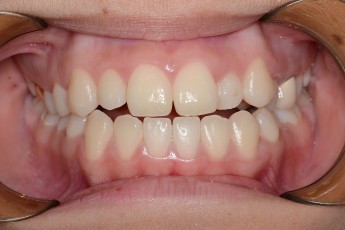

BEFORE & AFTER

- 덧니교정